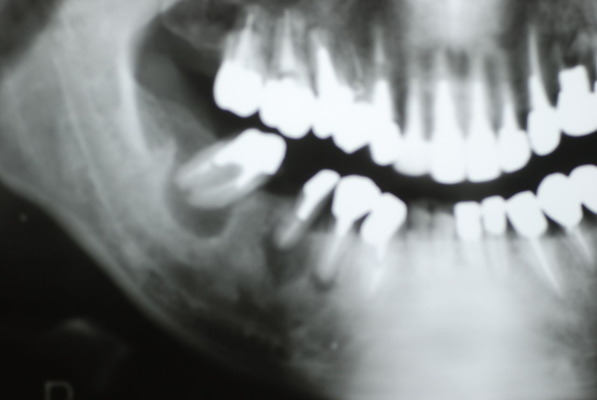

歯周病の疑いで東京のかなり遠方の方が来院されました。

驚くべきことですが、定期検診は受けていたそうです。しかしながら歯周病の指摘は受けたことがないそうです。

何故か?定期検診が虫歯のチェックのみになり、又肝心の歯周病の検査や歯周病の部分の予防や治療のためのブラシの使い方などを学んだ事がないのです。

本当に患者さんのことを考えると憂鬱になります。歯周病が悪化すると殆ど回復は無理だからです。